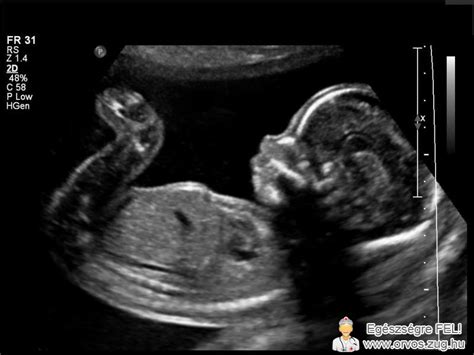

A méhen kívüli terhesség pontos diagnózisához vérvételre és ultrahangvizsgálatra van szükség. Habár a kismedence fizikális vizsgálata során és a jellegzetes tünetek miatt már gyanakodhatunk méhen kívüli terhességre, megbizonyosodni ultrahang- és vérvizsgálattal lehet.

Ultrahangvizsgálat: Ha a terhesség bizonyított, ultrahanggal mindenképp ellenőrizni kell a pontos helyét. Ugyanis a HCG hormon nem a méhből szabadul fel, méhen kívüli terhesség esetén is megemelkedik a szintje. Az ultrahang lehetővé teszi, hogy lássuk az embrió helyét. A hüvelyi ultrahangvizsgálat nagy képfelbontása révén, a közeli kismedencei szervek részletes vizsgálatát teszi lehetővé. Ezzel a módszerrel a nőgyógyász nagy biztonsággal meg tudja állapítani a terhesség tényét. Ha a méhen belül nem látható embrió, ez megerősíti méhen kívüli terhesség fennállásának lehetőségét. Ritkán előfordul, hogy a hüvelyi ultrahangvizsgálattal nem lehet látni a méhen kívüli terhességet, viszont a pozitív teszt terhességet feltételez.